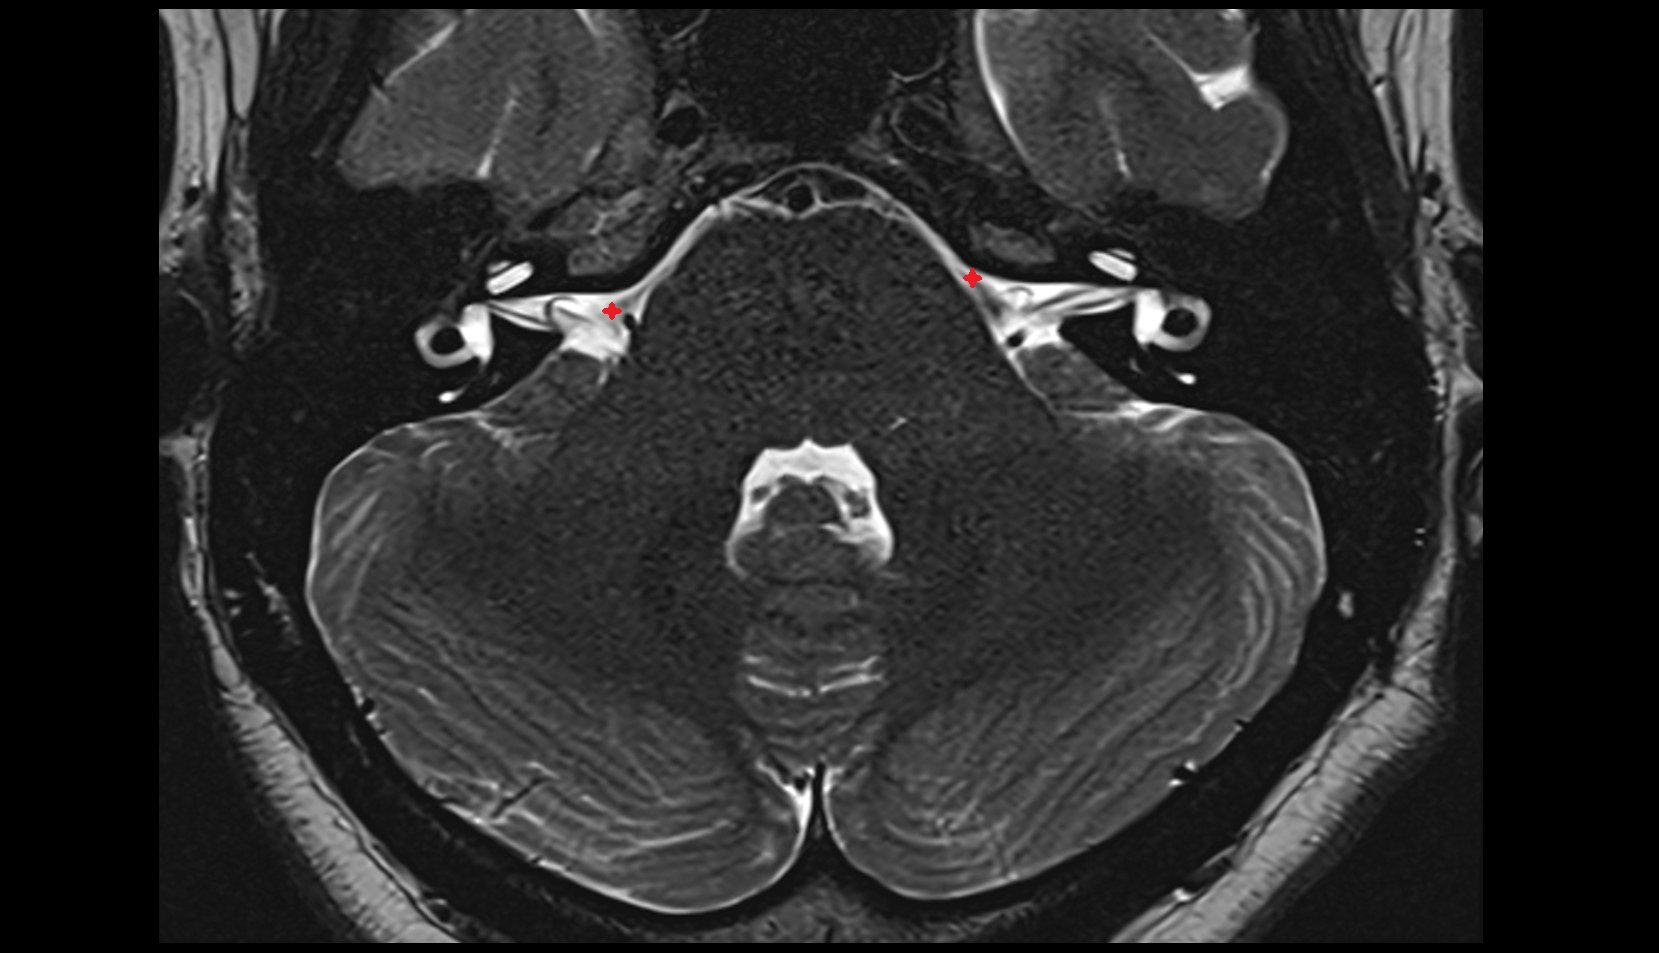

- Temporomandibular joint

- Mandibular condyle

- Mandibular fossa

- Articular disc of temporomandibular joint

- Articular eminence